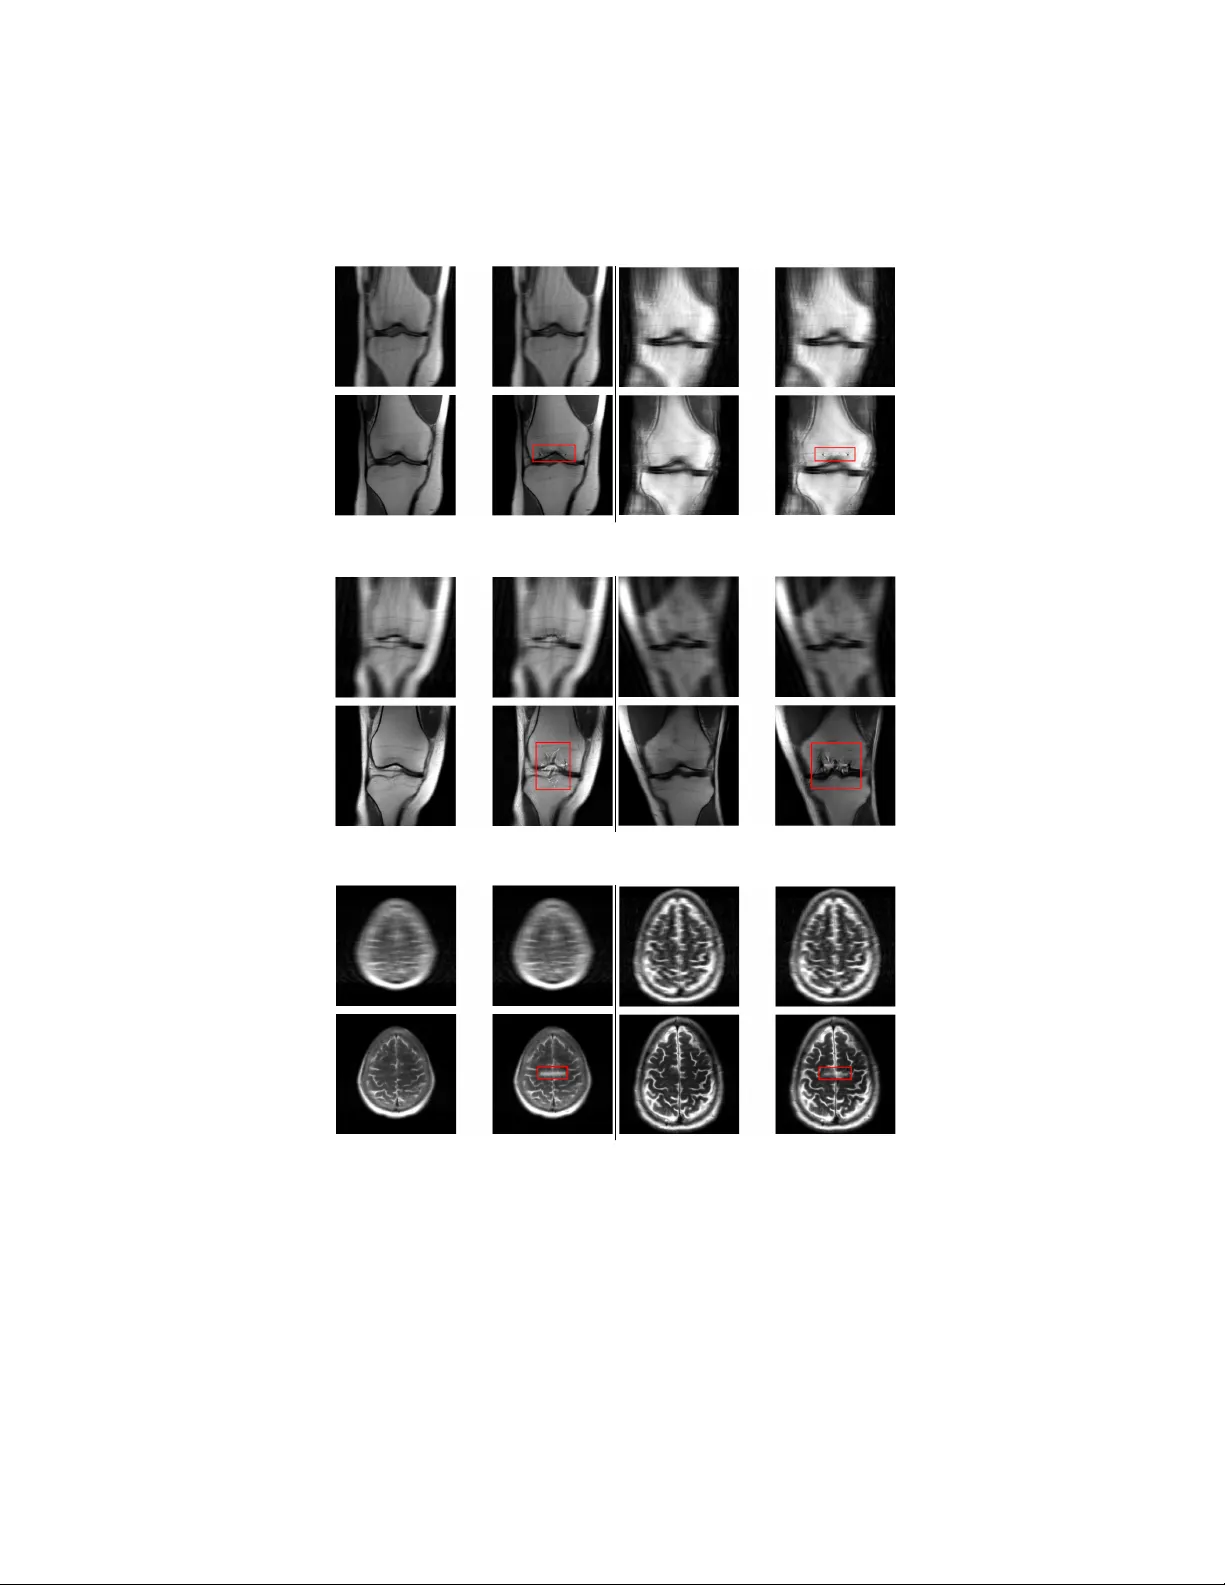

T riggering hallucinations in mo del-based MRI reconstruction via adv ersarial p erturbations Suna Buğda y 1 , Y v an Saeys 2 , 3 , and Jonathan P eck 2 , 3 ⋆ 1 F aculty of Engineering and Architecture/Computer Engineering, İzmir Bakırçay Univ ersity , İzmir, T urkey 2 Departmen t of Computer Science, Mathematics and Statistics, Ghen t Universit y , Ghen t, Belgium 3 Data Mining and Mo deling for Biomedicine Group, VIB Inflammation Researc h Cen ter, Ghen t, Belgium Abstract. Generativ e mo dels are increasingly used to impro ve the qual- it y of medical imaging, suc h as reconstruction of magnetic resonance images and computed tomograph y . How ever, it is well-kno wn that suc h mo dels are susceptible to hal lucinations : they may insert features into the reconstructed image whic h are not actually present in the original image. In a medical setting, such hallucinations ma y endanger patien t health as they can lead to incorrect diagnoses. In this work, we aim to quan tify the extent to whic h state-of-the-art generative mo dels suffer from hal- lucinations in the context of magnetic resonance image reconstruction. Sp ecifically , we craft adversarial p erturbations resembling random noise for the unprocessed input images which induce hallucinations when re- constructed using a generative model. W e perform this ev aluation on the brain and knee images from the fastMRI data set using UNet and end-to-end V arNet arc hitectures to reconstruct the images. Our results sho w that these models are highly susceptible to small perturbations and can be easily coaxed in to producing hallucinations. This fragilit y ma y partially explain wh y hallucinations occur in the first place and suggests that a carefully constructed adversarial training routine ma y reduce their prev alence. Moreo v er, these hallucinations cannot b e reli- ably detected using traditional image quality metrics. Nov el approac hes will th erefore need to b e developed to detect when hallucinations hav e o ccurred. Keyw ords: deep learning · computer vision · magnetic resonance imag- ing · robustness 1 In tro duction When patients go in for a medical scan, such as magnetic resonance imaging (MRI) or computed tomography (CT), the resulting images must first b e cleaned up or r e c onstructe d before they can b e used for diagnostic purp oses. There are ⋆ Corresp onding author: Jonathan.Peck@UGent.be 2 Buğda y et al. m ultiple reasons for this: patients never stay completely still during scans, whic h causes blurring; the physical measurement pro cess is sub ject to thermal noise and electromagnetic interference; etc [7]. Scanners also frequently undersample or ac c eler ate their measuremen ts, which can lead to aliasing and other artifacts due to incomplete data [30]. F or MRI, acceleration is usually p erformed to sav e costs and to increase patient comfort: a fully-sampled MRI would tak e several hours compared to the few min utes patients typically sp end inside suc h a scanner in practice [5]. F or CT, minimizing t he acquisition time is actually a necessit y due to the exp osure to a radioactiv e isotope which can damage tissues ov er an extended p eriod of time. (a) Ra w (b) FIST A (c) FIST A-Net Fig. 1. Comparison of classical FIST A and mo del-based FIST A-Net reconstruction of brain MR images. These images were taken from [3]. Naturally , there is a long line of research into prop er wa ys of reconstruct- ing medical imaging data [6, 12, 32, 42]. These “classical” algorithms are based on mathematical optimization problems and ha ve attractive theoretical guaran- tees, such as conv ergence rates and b ounds on the reconstruction error. More recen tly , the use of neural netw orks to reconstruct medical imaging data has b een explored [1, 3, 29, 46]. Sev eral studies hav e confirmed that the resulting reconstructions are more visually app ealing than those generated by classical algorithms [37, 38]. As an example, figure 1 compares the classical FIST A algo- rithm [6] to the more recen t mo del-based FIST A-Net metho d [3]. The impro ve- men t in visual quality is ob vious here. Nev ertheless, generativ e neural netw orks typically lack theoretical guaran- tees, calling their reliability in this context into question [28, 45]. Empirically , it is known that generativ e mo dels of any kind are susceptible to so-called hal luci- nations . Hallucinations occur when a generativ e mo del adds an imp ortan t feature to its output that w as not supp osed to b e there, or remov es a feature that should ha ve b een presen t. This problem is particularly well-kno wn in the field of lan- guage mo deling: mo dern large language mo dels (LLMs) are notoriously prone to generating con vincing misinformation or outright nonsense [24, 55]. Ho w ever, imaging mo dels are not exempt from this problem: a few examples are sho wn in figure 2. These alterations can hav e a significan t impact on patient care. As suc h, it is an important open problem to detect when suc h hallucinations ma y T riggering hallucinations in MRI reconstruction 3 (a) (b) Fig. 2. Examples of hallucinations introduced by model-based reconstructions of MR images. (a) In this image from [37], the model-based reconstruction in tro duces an additional sulcus in the brain whic h was not presen t in the original. (b) In this image tak en from [18], the mo del-based reconstruction remov es evidence of a meniscal tear that is presen t in the original data. ha ve o ccurred and to preven t them from happ ening if p ossible. Curren tly , there are no effectiv e metho ds to address these issues [30]. In this w ork, we aim to con tribute tow ards effective mitigation of hallucina- tions in medical imaging b y crafting an algorithm which actively pr ovokes them in state-of-the-art mo del-based reconstructions. Our motiv ation is that suc h an algorithm would facilitate follo w-up researc h into the detection and mitigation of hallucinations. F or instance, the algorithm could b e used to create a data set of reconstructions con taining hallucinations. Combined with clean reconstructions, a training data set can b e created to train a detector that flags hallucinations. Alternativ ely , the algorithm could also serve as a comp onent in an adversarial training regime that improv es the robustness of generativ e models suc h that hallucinations o ccur less frequen tly . W e ev aluate our attack on the fastMRI data set [56] against UNet [43] and E2E-V arNet [46] mo dels, which hav e been found to obtain go od perfor- mance on these reconstruction tasks. Our attack seems to be highly successful at eliciting hallucinations via imperceptibly small p erturbations of the input, leading to the conclusion that these mo dels are highly unstable and hallucina- tions can easily arise in practice purely as a result of noise. W e perform fur- ther exp erimen ts to attempt to detect the hallucinations using standard im- age qualit y metrics, suc h as p eak signal-to-noise ratio (PSNR), normalized ro ot mean squared error (NRMSE) and structural similarity index (SSIM; [53]). W e find that the distributions of these metrics ov erlap almost completely and hence cannot be used to distinguish reliable reconstructions from those con- taining hallucinations. The code to repro duce our exp erimen ts is a v ailable at https://github.com/saeyslab/adversarial- mri . 2 Bac kground Man y imaging reconstruction problems are essentially instances of a particular line ar inverse pr oblem [41, 51]. F ormally , w e observ e some noisy vector y ∈ C m 4 Buğda y et al. whic h is assumed to b e pro duced according to a so-called forwar d mo del : y = Φ · x ♮ + e . (1) Here, x ♮ ∈ C n is the true signal, Φ ∈ C m × n is a measuremen t matrix (also referred to as the forwar d tr ansform ) and e ∈ C m is noise. W e alwa ys hav e m < n , so the original signal x ♮ is sub ject to b oth compression (via Φ ) and additiv e noise (giv en by e ). The goal is to reconstruct x ♮ as faithfully as p ossible giv en the noisy and compressed observ ations y . MRI and CT scans present t ypical examples of linear in verse problems. In CT, the observ ations y are sinograms obtained via X-ra y pro jections of the original image x ♮ from v arious directions [57]. In the case of MRI, the observ ations are spatial frequencies in F ourier space, referred to as k-sp ac e in the literature [30]. Mathematically , the measurement matrices of CT and MRI are giv en b y the discrete Radon transform [8] and discrete F ourier transform [54], resp ectiv ely . The solutions to linear inv erse problems are typically obtained via iterative optimization pro cedures based on a probabilistic mo del of the noise and the forw ard transform. The conditional densit y p Y | X ( y | x ) is usually known from the ph ysics of the measurement process. The most common choice is to assume Gaussian noise, so that y is normally distributed around Φ · x ♮ . This leads to an optimization problem kno wn as b asis pursuit [16]: ˆ x = arg min x ∈ C n 1 2 ∥ y − Φ · x ∥ 2 2 + λ R ( x ) . (2) The L 2 p enalt y is referred to as the data c onsistency obje ctive and is a direct result of the Gaussian assumption on e . The second term, R ( x ) , is a regularizer whic h dep ends on the choice of prior p X ( x ) . Common choices for R include the L 1 norm in image space, ∥ x ∥ 1 ; the L 1 norm in w a velet space, ∥ Ψ · x ∥ 1 , where Ψ is a discrete wa velet transform [49]; or the total v ariation of x [14]. The resulting reconstruction algorithms are well-documented in v arious surv eys and textb ooks [25]. 2.1 Mo del-based reconstruction The success of deep learning approac hes in the image domain suggests that deep neural netw orks may hav e potential in determining go od solutions to linear in verse problems for medical imaging. While it is possible to train a neural net work to directly learn the mapping from the observ ation space to the original image space [29], this strategy p oses the risk of hallucinations [9, 28, 30] and lac ks formal guarantees on the reconstruction qualit y . In particular, when a neural netw ork is used to reconstruct the image directly , it is not clear what the underlying inv erse problem actually is that is b eing solved, which casts doubt on the reliabilit y of the results [45]. In ligh t of these issues, some authors hav e attempted to use deep netw orks as a regularizer rather than a full reconstruction algorithm. Specifically , they retain the original optimization problem (2) but incorp orate the neural netw ork into T riggering hallucinations in MRI reconstruction 5 the regularizer R ( x ) . This is the approach tak en by the MoDL framework [1], whic h reconstructs the image by solving (2) with R ( x ) = ∥ x − F θ ( x ) ∥ 2 2 , where F θ is a trained denoising neural netw ork. In this case, the regularization consists of minimizing the estimated noise in the image as determined by a neural net work reconstruction. 2.2 A dversarial perturbations A dversarial p erturbations are w orst-case alterations of the inputs to a mac hine learning model, in the sense that they are intended to b e imp erceptible or harm- less to a human observer while causing mo dels to make mistakes [48]. In the image domain, they typically tak e the form of (nearly) imp erceptible distor- tions. F or discriminativ e mo dels, the goal of adv ersarial p erturbations is usually to cause misclassification. In the case of generative models, performance is gener- ally harder to quan tify but usually relies on minimizing some measure of similar- it y b et ween the output of the model and a reference. Examples include the mean squared error (MSE) or the structural similarit y index measure (SSIM) [53]. A dversarial perturbations hav e been the sub ject of muc h researc h for a long time no w [10, 11], and while certain promising defenses ha ve b een prop osed, the problem is still far from b eing considered “solved” in an y meaningful wa y [21, 40]. In this w ork, we will make use of adversarial p erturbations to craft imperceptible distortions that, when added to an MR image, result in hallucinations when reconstructed b y a neural netw ork. 2.3 Related w ork A dversarial p erturbations for medical images are not ne w, and many attacks and defenses ha ve b een prop osed to date [23, 31]. Ho wev er, the v ast ma jority of existing w ork fo cuses on classification tasks, which is the most straightforw ard setting for an adversarial attac k because success is easy to measure through misclassification rate. By con trast, w e fo cus here on attac king r e c onstruction tasks, which is a generativ e setting where the ob jective is to remo ve undesirable artifacts from the data and impro ve visual qualit y . In this vein, [22] also consider the UNet and E2E-V arNet mo dels we study here and compare their robustness to classical metho ds suc h as total v ariation (TV) minimization. They find that b oth neural net works as w ell as classical re- construction algorithms are vulnerable to adv ersarial p erturbations sp ecifically tailored to the metho ds in question. This finding seems to con tradict other stud- ies such as [26] who claim that TV minimization is prov ably robust. In fact, [26] further find that neural net works are resilient against adv ersarial perturbations, whic h also con tradicts our o wn results. Although the existing bo dy of w ork on robustness of image reconstruction seems to fav or the view that classical recon- struction algorithms are stable whereas neural netw orks are not, consensus on this question do es not seem to ha ve b een reached y et. 6 Buğda y et al. Theoretical results on the stability of classical reconstruction algorithms hav e b een obtained b y [2]. F rom their w ork, w e can conclude that classical metho ds should not suffer from the same instability with resp ect to small p erturbations, giv en the fav orable contin uity properties these metho ds enjoy . [20] prov e several results related to the (non-)existence of accurate and stable neural net works for in verse problems. They also in tro duce FIRENET s, a family of neural net works that can b e efficien tly trained and hav e prov able stability properties. More re- cen tly , [28] related the instabilities of model-based reconstruction methods to the k ernel of the measurement matrix. Their main results are broadly applicable to man y reconstruction algorithms (not merely neural netw orks), and consist of a few “no free lunch” theorems which sho w that (paradoxically) higher p erfor- mance increases the probabilit y of hallucination, and that hallucinations are not rare ev ents (in the sense of ha ving non-zero probability of occurring). The work that comes closest to ours is [36], who also study adv ersarial per- turbations for MRI reconstruction. They ev aluate adversarial attacks against UNet [43] and E2E-V arNet [46] on the fastMRI data set [56]. These attacks are untargeted in the sense that they aim to maximize the reconstruction error within a sp ecified region with respect to fully sampled reference images. By con- trast, in this work, w e study a targeted adv ersarial attack which aims to insert a specific detail into the reconstruction that is not actually present. This attac k requires no reference data and supp orts any type of detail whic h can be effi- cien tly rendered on to an image. W e also p erform additional exp erimen ts in an attempt to detect the hallucinations we inserted using standard image quality metrics, suc h as PSNR, NRMSE and SSIM, and find that these are ineffective. 3 Metho d The goal of our attac k is to craft invisible p erturbations suc h that mo del- based reconstructions of the p erturbed data p oin ts exhibit distortions that could mislead diagnostic interpretation. T o achiev e this, given a k -space data v ector z ∈ C n and a reconstruction map F : C n → R n , we solve the following opti- mization problem: δ ⋆ = arg min δ ∈ C n ∥ m ⊙ ( F ( z + δ ) − y t ) ∥ 2 2 ∥ m ∥ 1 + ∥ (1 − m ) ⊙ ( F ( z + δ ) − F ( z )) ∥ 2 2 ∥ 1 − m ∥ 1 (3) sub ject to the constraint ∥ δ ∥ ∞ ≤ ε , where ε > 0 is the p erturbation budget, m ∈ R n is a binary mask, and y t is a target reconstruction. The budget ε m ust b e sufficien tly small so that the generated perturbations are in visible to the nak ed ey e, but large enough to allow insertion of the desired hallucinations in the reconstruction. The sp ecific v alue therefore depends on the application; see section 4 for further details. The target reconstruction y t is designed by drawing a short white line in the center of the original reconstruction F ( z ) . The mask m delimits the region T riggering hallucinations in MRI reconstruction 7 where this line was added. In this wa y , the ob jectiv e function in (3) strikes a balance b etw een the insertion of the specified detail on the one hand and faithful reconstruction of the image on the other: the first term in the loss penalizes the difference betw een the reconstruction and the target image, whereas the second term p enalizes the difference betw een the reconstruction and the ground truth. The optimal solution is achiev ed when the p erturbation δ is such that F ( z + δ ) is identical to y t within the target region defined by the mask m and iden tical to F ( z ) outside the target region. Pseudo code describing the attac k is pro vided in appendix A. The method is inspired by the basic iterativ e method (BIM), which is a popular algorithm for generating adv ersarial examples [33]. Note that k -space data is complex-v alued, but w e consider only real-v alued perturbations δ in our algorithm. This is done to simplify the computations on the one hand, but also b ecause w e noticed that, for our purposes, it suffices to only perturb the real components of the k -space v ector. Hence we lea ve the imaginary components of all samples unc hanged. Although in this work we only consider lines drawn onto the center of the image, the attack we dev elop ed here is agnostic to the sp ecific target. Indeed, the attack can use an y target y t with asso ciated mask m and hence can be used to prov oke all kinds of hallucinations, as long as they can be efficien tly rendered on to an image. W e c hose lines here because they are simple y et already highly effectiv e at introducing unw anted artifacts, but other shapes such as squares or circles ma y also be used. An in teresting further exp eriment could b e to use parts of other images, which include real pathologies, and render them onto images whic h do not contain them. In this wa y , a convincing meniscal tear might b e hallucinated on to an image of a healthy knee, for instance. This can b e facilitated using annotations of pathologies in existing MRI data sets, such as fastMRI+. 4 4 Exp erimen ts W e ev aluated our attack algorithm on the fastMRI data set [56] using a pre- trained UNet [43] and E2E-V arNet [46]. W e consider single-coil and m ulti-coil knee images, as w ell as m ulti-coil brain images. W e do not ev aluate E2E-V arNet on the single-coil knee images, since there were no pretrained c heckpoints a v ail- able for that model on this part of the fastMRI data set. The adversarial p ertur- bations are generated by solving (3) using algorithm A.1 with T = 150 iterations. The magnitude of the perturbation w as b ounded in the L ∞ norm to a maxim um of ε = 1 × 10 − 6 with a step size of α = 1 × 10 − 7 . 4.1 Results W e p erformed a quan titativ e ev aluation of the results using peak signal-to-noise ratio (PSNR), normalized ro ot mean squared error (NRMSE), and structural similarit y index measure (SSIM). These metrics are computed separately for the 4 https://github.com/microsoft/fastmri- plus 8 Buğda y et al. pairs of original and perturb ed input samples, as well as the pair of original and p erturbed reconstructions. W e also inv estigated the v alue of the ob jective function in (3) and found that it was almost alw ays negligibly small across all mo dels and data sets (on the order of 10 − 8 or less). W e therefore do not include these v alues in the rep ort, but we conclude that they are indicative of a successful attac k. T able 1. Summary statistics of the exp eriments. The rep orted num b ers are means o ver the en tire data set along with their standard deviations in parentheses. Mo del Data PSNR ↑ NRMSE ↓ SSIM ↑ UNet sc-knee 55.60 (6.18) 0.01 (0.01) 1.00 (0.00) 34.24 (10.10) 0.17 (0.33) 0.95 (0.10) mc-knee 50.35 (5.74) 0.02 (0.01) 1.00 (0.00) 28.48 (4.62) 0.23 (0.13) 0.82 (0.13) mc-brain 61.72 (4.58) 0.01 (0.00) 1.00 (0.00) 26.00 (11.06) 0.76 (1.07) 0.68 (0.34) V arNet mc-knee 50.69 (6.24) 0.02 (0.01) 1.00 (0.01) 31.70 (1.70) 0.42 (0.18) 0.93 (0.03) mc-brain 60.10 (4.44) 0.01 (0.00) 1.00 (0.00) 41.72 (7.48) 0.10 (0.10) 0.98 (0.03) Summary statistics of these metrics are given in table 1, with v alues rounded to tw o decimal places. F or ev ery metric M ∈ { PSNR , NRMSE , SSIM } , w e report the mean and standard deviation of t wo v alues across the data set: 1. The metric computed on the zero-filled 5 original and adv ersarial input sam- ples, M (ZF( z ) , ZF( z + δ )) , where ZF( · ) denotes the zero-filling op eration. 2. The metric computed on the reconstructions, M ( F ( z ) , F ( z + δ )) . W e rep ort these tw o v alues for each metric to gauge the success of the attac k: in eac h case, we expect the metric computed on the zero-filled pair to b e “goo d” – high in the case of PSNR and SSIM, low for NRMSE – but the reconstructions should b e noticeably worse. W e do indeed observe this pattern in table 1: the metric v alues are consisten tly b etter for the zero-filled originals compared to the reconstructions. F or the originals, PSNR v alues are alwa ys at least 50 dB, the NRMSE is 0.02 or less and the SSIM is almost 100%. This suggests that the clean input samples and the adversarial samples are visually indistinguishable, as desired. On the other hand, the metric v alues for the reconstructed samples are noticeably worse: PSNR v alues drop to around 40 dB or less, NRMSE in- creases b y at least an order of magnitude and SSIM v alues can drop up to thirty 5 Zero-filling is the most basic reconstruction method where w e simply apply an inv erse F ourier transform on the ra w k -space data (possibly padded with additional zeros), without making an y attempt at reducing noise. T riggering hallucinations in MRI reconstruction 9 p ercen tage points. Although these v alues still indicate that the reconstructions are similar, there is a significan t difference. Moreov er, it is expected for the re- constructions to retain muc h similarity , b ecause the artificial detail we added using our adv ersarial attack only co vers a small portion of the image. 10 20 30 40 50 60 70 80 PSNR 1 0 3 1 0 2 1 0 1 1 0 0 MSE 0.4 0.5 0.6 0.7 0.8 0.9 1.0 value S SIM original adversarial (a) sc-knee 20 30 40 50 60 PSNR 1 0 2 1 0 1 MSE 0.5 0.6 0.7 0.8 0.9 1.0 value S SIM original adversarial (b) mc-knee 0 10 20 30 40 50 60 70 PSNR 1 0 2 1 0 1 1 0 0 MSE 0.2 0.4 0.6 0.8 1.0 value SSIM original adversarial (c) mc-b rain Fig. 3. Distributions of the metric v alues for the UNet model. T o further in vestigate the extent to whic h our attack can b e called successful, w e plot the full distributions of the metric v alues in figure 3 for the UNet mo del and figure 4 for the V arNet mo del. These v alues are visualized as histogram- based ridge plots, showing the o v erlap b etw een the distributions. Note that the MSE v alues are sho wn on a semi-logarithmic scale. Consisten t with table 1, we obse rv e that the distributions of all metric v alues tend to b e well-separated b etw een the original samples and the reconstructions. Some exceptions to this can b e observed: the distributions of NRMSE for the sc-knee data reconstructed by the UNet model largely ov erlap, as do the distri- butions of SSIM v alues for the sc-knee data reconstructed by the UNet mo del and mc-brain data reconstructed b y the E2E-V arNet mo del. In all of these cases, ho wev er, w e observe that the metrics inv olved hav e a significan tly larger spread after reconstruction. This indicates that the hallucinated details may not alwa ys b e v ery visible, but given the large v ariance in the v alues, the attac k is still v ery lik ely to pro duce noticeable distortions for the ma jority of inputs. A qualitative assessment of the generated images was also performed but has b een deferred to app endix B due to space constraints. F rom those results, 10 Buğday et al. 25 30 35 40 45 50 55 60 PSNR 1 0 2 1 0 1 1 0 0 MSE 0.86 0.88 0.90 0.92 0.94 0.96 0.98 1.00 value SSIM original adversarial (a) mc-knee 30 40 50 60 70 PSNR 1 0 2 1 0 1 MSE 0.90 0.92 0.94 0.96 0.98 1.00 value S SIM original adversarial (b) mc-b rain Fig. 4. Distributions of the metric v alues for the E2E-V arNet model. w e conclude that the adversarially p erturbed samples can lead to realistic re- constructions whic h exhibit biologically plausible distortions that could mislead exp ert interpretation, and that the insertion of the artificial detail will often cause further distortion far b ey ond the target region delineated by our mask. 4.2 Detecting hallucinations In this section, we turn to the question of detectability of our generated hal- lucinations. W e consider a simple threat mo del where an adversary may hav e con taminated part of a data set using p erturbations generated b y algorithm A.1. The defender is given access only to k -space vectors z 1 , . . . , z N and must decide whic h (if any) of the samples ha ve been corrupted. As argued abov e, it is exp ected that classical reconstruction algorithms suc h as total v ariation, conjugate gradients and FIST A do not suffer from hallucina- tions. It therefore stands to reason that suc h algorithms may b e used to compute an expected distribution of residual reconstruction errors against which we may test the mo del-based reconstructions. Specifically , giv en a p otentially p erturbed k -space vector z , we ask whether it is possible to detect hallucinations using standard image quality metrics applied to the pair R ( z ) and F ( z ) , where R ( · ) denotes some classical reconstruction algorithm. W e test this hypothesis b y first using algorithm A.1 to generate a data set of p erturbed k -space vectors ˜ z 1 , . . . , ˜ z N . Then, for each unp erturb ed k -space v ector z and its adversarially p erturbed coun terpart ˜ z , we compute PSNR, NRMSE and SSIM metrics on the pairs of reconstructions (TV ( z ) , F ( z )) and (TV( ˜ z ) , F ( ˜ z )) , where TV( · ) is the total v ariation reconstruction algorithm as implemented in the SigPy library 6 using sensitivity maps estimated by ESPIRiT [52]. If these distributions are well-separated, then the defender can simply compute these metrics for eac h sample in the data set and compare them to a pre-determined threshold. The distributions of the resulting v alues are given in figure 5 for the UNet mo del and figure 6 for the E2E-V arNet mo del. F rom these results w e observe 6 https://github.com/mikgroup/sigpy T riggering hallucinations in MRI reconstruction 11 5.0 7.5 10.0 12.5 15.0 17.5 20.0 22.5 PSNR 1 0 0 3 × 1 0 1 4 × 1 0 1 6 × 1 0 1 MSE 0.20 0.25 0.30 0.35 0.40 0.45 0.50 0.55 0.60 value S SIM original adversarial (a) sc-knee 10 12 14 16 18 20 22 PSNR 1 0 0 4 × 1 0 1 6 × 1 0 1 2 × 1 0 0 MSE 0.40 0.45 0.50 0.55 0.60 0.65 value S SIM original adversarial (b) mc-knee 5 10 15 20 25 PSNR 1 0 0 4 × 1 0 1 6 × 1 0 1 MSE 0.1 0.2 0.3 0.4 0.5 0.6 0.7 value SSIM original adversarial (c) mc-b rain Fig. 5. Distributions of the metric v alues for the UNet mo del using total v ariation reconstructions. that, for every metric, the tw o distributions almost en tirely ov erlap. The only exception seems to b e the SSIM metric on the mc-brain data for the UNet mo del, whic h exhibits an unusual p eak near 10%. How ever, this pattern never repeats for an y of the other data sets and do es not app ear at all for the E2E-V arNet mo del. It therefore seems unreliable, and the distributions still ov erlap sufficiently to mak e any attempt at separation using the SSIM prone to error. W e stress that algorithm A.1 w as not explicitly constructed to maximize o verlap b et ween these metrics. Indeed, our attac k merely minimizes (3) and does not mak e any use of other reconstruction algorithms, nor do es it directly opti- mize PSNR or SSIM. Y et it appears this approac h already suffices to make the generated hallucinations essentially undetectable using standard image qualit y metrics. As is common practice in adv ersarial attac ks [50], algorithm A.1 may b e extended by including such additional ob jectives in to the loss function in order to mak e the p erturbations ev en less detectable, but it seems this is not necessary here. Note that we do not explore the possibility of training mo del-based detectors for these perturbations here. This omission is due to our exp ectation that suc h approac hes are b ound to be ineffective, since the field of adv ersarial mac hine learning has learned through exp erience [4, 13, 40, 50] that adversarial attacks can b e easily adapted to incorp orate the outputs of such detectors. Hence, an ev aluation where we train a neural netw ork to differentiate b et ween clean and 12 Buğday et al. 8 10 12 14 16 PSNR 1 0 1 MSE 0.10 0.15 0.20 0.25 0.30 0.35 0.40 0.45 value SSIM original adversarial (a) mc-knee 10 12 14 16 18 20 22 PSNR 1 0 0 6 × 1 0 1 2 × 1 0 0 3 × 1 0 0 4 × 1 0 0 MSE 0.40 0.45 0.50 0.55 0.60 0.65 value S SIM original adversarial (b) mc-b rain Fig. 6. Distributions of the metric v alues for the E2E-V arNet model using total v aria- tion reconstructions. p erturbed k -space v ectors w ould merely serv e to create a false sense of security , and w ould likely result in a swift break of the detector in a follo w-up work. These findings suggest that, in order to solve the problem of hallucinations in mo del-based MRI reconstructions, mathematically principled approaches will b e needed that give rise to c ertifie d defenses or detectors. In this vein, carefully constructed adversarial training regimes [34, 35] or the application of denoised smo othing [19, 44] may b e explored. 5 Conclusions W e hav e proposed an adv ersarial attac k which can insert hallucinations in to mo del-based MRI reconstructions via invisible perturbations of the input sam- ples. W e ev aluated the algorithm using several image quality metrics and found that it often succeeds in causing significan t distortion of the reconstructed sam- ples while remaining invisible to the naked ey e in input space. Our results imply that, in the absence of reference data, such distortions are not easily detected using “traditional” metrics suc h as p eak signal-to-noise ratio, mean squared error or structural similarit y index. Moreov er, a qualitative assessmen t of the results indicates that whenev er our attack is successful, it tends to cause further biolog- ically plausible distortions b ey ond the neighborho o d of the artificially inserted detail. W e conclude that state-of-the-art mo del-based MRI reconstruction algorithms are highly unstable with respect to small noise and can easily b e induced to in- sert hallucinatory structures. This p oses a risk when these mo dels are used in medical con texts, where such p erturbations ma y arise sp on taneously through noise and ma y affect diagnosis and even tual treatmen t of patients. F uture w ork in this area should fo cus on reducing the instability of reconstruction maps to small p erturbations as well as developing detection mec hanisms whic h can signal when reconstructions ma y b e unreliable. The attack in tro duced in this work ma y form the basis for an adversarial training regime that could impro ve the robust- T riggering hallucinations in MRI reconstruction 13 ness of mo del-based MRI reconstruction or serv e as a baseline against which to b enc hmark p oten tial detection approaches. Giv en the historical failure of many approac hes to detecting adversarial p er- turbations, w e argue that future researc h in this direction should fo cus on mathe- matically principled tec hniques that lead to detectors with prov able correctness ev en in the presence of w orst-case perturbations. It is kno wn that detecting adv ersarial p erturbations is a very hard problem in general, and no satisfying general-purp ose solutions exist at this time [11, 40]. How ever, when the problem is constrained specifically to the detection of hallucinations in MRI reconstruction, existing mathematical results in compressed sensing may b e employ ed whic h are not av ailable in more general settings [17, 39, 47]. It is our hop e that this may lead to pro v able solutions to the problem of hallucinations in mo del-based MRI reconstruction. A ckno wledgmen ts. Suna Buğday w as supp orted by an Erasmus+ mobility grant during her sta y at Ghent Universit y . References 1. Aggarw al, H.K., Mani, M.P ., Jacob, M.: MoDL: Model-based deep learning archi- tecture for inv erse problems. IEEE transactions on medical imaging 38 (2), 394–405 (2018) 2. del Aguila Pla, P ., Neuma yer, S., Unser, M.: Stabilit y of image-reconstruction algorithms. IEEE T ransactions on Computational Imaging 9 , 1–12 (2023) 3. Aromal, C., Datta, S.: FIST A-NET: Compressed sensing MRI reconstruction us- ing unrolled iterative netw orks. In: 2024 IEEE 21st India Council International Conference (INDICON). pp. 1–6. IEEE (2024) 4. A thalye, A., Carlini, N., W agner, D.: Obfuscated gradients give a false sense of securit y: Circumv enting defenses to adversarial examples. In: International confer- ence on mac hine learning. pp. 274–283. PMLR (2018) 5. Ballinger, J., Wilczek, M., Knip e, H.: Acquisition time (Apr 2013). https://doi. org/10.53347/rid- 22553 , http://dx.doi.org/10.53347/rID- 22553 6. Bec k, A., T eboulle, M.: A fast iterativ e shrink age-thresholding algorithm for linear in verse problems. SIAM journal on imaging sciences 2 (1), 183–202 (2009) 7. Bellon, E.M., Haac ke, E.M., Coleman, P .E., Sacco, D.C., Steiger, D.A., Gangarosa, R.E.: MR artifacts: a review. American Journal of Ro en tgenology 147 (6), 1271– 1281 (1986) 8. Beylkin, G.: Discrete Radon transform. IEEE transactions on acoustics, sp eech, and signal processing 35 (2), 162–172 (1987) 9. Bhadra, S., Kelk ar, V.A., Brooks, F.J., Anastasio, M.A.: On hallucinations in to- mographic image reconstruction. IEEE transactions on medical imaging 40 (11), 3249–3260 (2021) 10. Biggio, B., Corona, I., Maiorca, D., Nelson, B., Šrndić, N., Lask ov, P ., Giacinto, G., Roli, F.: Ev asion attac ks against machine learning at test time. In: Joint Europ ean conference on machine learning and kno wledge disco very in databases. pp. 387–402. Springer (2013) 11. Biggio, B., Roli, F.: Wild patterns: T en years after the rise of adv ersarial mac hine learning. In: Proceedings of the 2018 ACM SIGSA C Conference on Computer and Comm unications Securit y . pp. 2154–2156 (2018) 14 Buğday et al. 12. Blo c k, K.T., Ueck er, M., F rahm, J.: Undersampled radial MRI with multiple coils. Iterativ e image reconstruction using a total v ariation constrain t. Magnetic Reso- nance in Medicine: An Official Journal of the International So ciety for Magnetic Resonance in Medicine 57 (6), 1086–1098 (2007) 13. Carlini, N., W agner, D.: Adv ersarial examples are not easily detected: Bypassing ten detection metho ds. In: Pro ceedings of the 10th ACM w orkshop on artificial in telligence and security . pp. 3–14 (2017) 14. Cham b olle, A., Caselles, V., Cremers, D., Nov aga, M., Pock, T., et al.: An introduc- tion to total v ariation for image analysis. Theoretical foundations and n umerical metho ds for sparse reco very 9 (263-340), 227 (2010) 15. Chattopadh ya y , N., Chattopadh ya y , A., Gupta, S.S., Kasper, M.: Curse of dimen- sionalit y in adv ersarial examples. In: 2019 International Joint Conference on Neural Net works (IJCNN). pp. 1–8. IEEE (2019) 16. Chen, S., Donoho, D.: Basis pursuit. In: Proceedings of 1994 28th Asilomar Con- ference on Signals, Systems and Computers. v ol. 1, pp. 41–44. IEEE (1994) 17. Chen, Y., Caramanis, C., Mannor, S.: Robust sparse regression under adversarial corruption. In: In ternational conference on machine learning. pp. 774–782. PMLR (2013) 18. Cheng, K., Caliv á, F., Shah, R., Han, M., Ma jumdar, S., Pedoia, V.: A ddress- ing The F alse Negative Problem of Deep Learning MRI Reconstruction Mo d- els by Adv ersarial A ttacks and Robust T raining. In: Arb el, T., Ben A y ed, I., de Bruijne, M., Descoteaux, M., Lombaert, H., Pal, C. (eds.) Pro ceedings of the Third Conference on Medical Imaging with Deep Learning. Pro ceedings of Mac hine Learning Research, vol. 121, pp. 121–135. PMLR (06–08 Jul 2020), https://proceedings.mlr.press/v121/cheng20a.html 19. Cohen, J., Rosenfeld, E., K olter, Z.: Certified adversarial robustness via random- ized smo othing. In: in ternational conference on mac hine learning. pp. 1310–1320. PMLR (2019) 20. Colbro ok, M.J., Antun, V., Hansen, A.C.: The difficulty of computing stable and accurate neural netw orks: On the barriers of deep learning and Smale’s 18th prob- lem. Pro ceedings of the National Academ y of Sciences 119 (12), e2107151119 (2022) 21. Costa, J.C., Roxo, T., Pro ença, H., Inacio, P .R.M.: How deep learning sees the w orld: A surv ey on adv ersarial attac ks & defenses. IEEE A ccess 12 , 61113–61136 (2024) 22. Darestani, M.Z., Chaudhari, A.S., Hec kel, R.: Measuring robustness in deep learn- ing based compressive sensing. In: International Conference on Machine Learning. pp. 2433–2444. PMLR (2021) 23. Dong, J., Chen, J., Xie, X., Lai, J., Chen, H.: Survey on adv ersarial attack and defense for medical image analysis: Methods and challenges. A CM Computing Surv eys 57 (3), 1–38 (2024) 24. F arquhar, S., Kossen, J., Kuhn, L., Gal, Y.: Detecting hallucinations in large lan- guage mo dels using seman tic en tropy . Nature 630 (8017), 625–630 (2024) 25. F oucart, S., Rauh ut, H.: A Mathematical Introduction to Compressiv e Sens- ing. Springer New Y ork (2013). https://doi.org/10.1007/978- 0- 8176- 4948- 7 , http://dx.doi.org/10.1007/978- 0- 8176- 4948- 7 26. Genzel, M., Macdonald, J., März, M.: Solving inv erse problems with deep neu- ral netw orks – robustness included? IEEE transactions on pattern analysis and mac hine in telligence 45 (1), 1119–1134 (2022) 27. Gilmer, J., Metz, L., F aghri, F., Schoenholz, S., Ragh u, M., W atten b erg, M., Go odfellow, I.: Adv ersarial spheres (2018), https://openreview.net/forum?id= SyUkxxZ0b T riggering hallucinations in MRI reconstruction 15 28. Gottsc hling, N.M., Antun, V., Hansen, A.C., A dco c k, B.: The troublesome kernel: On hallucinations, no free lunc hes, and the accuracy-stability tradeoff in inv erse problems. SIAM Review 67 (1), 73–104 (2025) 29. Hammernik, K., Klatzer, T., Kobler, E., Rec ht, M.P ., Sodickson, D.K., Pock, T., Knoll, F.: Learning a v ariational netw ork for reconstruction of accelerated MRI data. Magnetic resonance in medicine 79 (6), 3055–3071 (2018) 30. Hec kel, R., Jacob, M., Chaudhari, A., Perlman, O., Shimron, E.: Deep learn- ing for accelerated and robust MRI reconstruction: a review. arXiv preprint arXiv:2404.15692 (2024) 31. Ka viani, S., Han, K.J., Sohn, I.: Adv ersarial attacks and defenses on ai in medical imaging informatics: A survey . Expert Systems with Applications 198 , 116815 (2022) 32. Ka wata, S., Nalcioglu, O.: Constrained iterative reconstruction by the conjugate gradien t method. IEEE transactions on medical imaging 4 (2), 65–71 (2007) 33. Kurakin, A., Goo dfellow, I.J., Bengio, S.: Adv ersarial examples in the physical w orld. In: Artificial in telligence safet y and securit y , pp. 99–112. Chapman and Hall/CR C (2018) 34. Lee, S., Lee, W., Park, J., Lee, J.: T ow ards b etter understanding of train- ing certifiably robust models against adversarial examples. In: Ranzato, M., Beygelzimer, A., Dauphin, Y., Liang, P ., V aughan, J.W. (eds.) A dv ances in Neu- ral Information Pro cessing Systems. v ol. 34, pp. 953–964. Curran Asso ciates, Inc. (2021), https://proceedings.neurips.cc/paper_files/paper/2021/file/ 07c5807d0d927dcd0980f86024e5208b- Paper.pdf 35. Mao, Y., Müller, M., Fischer, M., V ec hev, M.: Connecting certified and adversarial training. A dv ances in Neural Information Processing Systems 36 , 73422–73440 (2023) 36. Morsh uis, J.N., Gatidis, S., Hein, M., Baumgartner, C.F.: A dversarial robustness of MR image reconstruction under realistic perturbations. In: International W orkshop on Machine Learning for Medical Image Reconstruction. pp. 24–33. Springer (2022) 37. Muc kley , M.J., Riemenschneider, B., Radmanesh, A., Kim, S., Jeong, G., Ko, J., Jun, Y., Shin, H., Hw ang, D., Mostapha, M., et al.: State-of-the-art mac hine learn- ing MRI reconstruction in 2020: Results of the second fastMRI challenge. arXiv preprin t arXiv:2012.06318 2 (6) (2020) 38. Muc kley , M.J., Riemenschneider, B., Radmanesh, A., Kim, S., Jeong, G., Ko, J., Jun, Y., Shin, H., Hw ang, D., Mostapha, M., et al.: Results of the 2020 fastMRI c hallenge for machine learning MR image reconstruction. IEEE transactions on medical imaging 40 (9), 2306–2317 (2021) 39. P eck, J., Goossens, B.: Robust width: A ligh tw eight and certifiable adversarial defense. arXiv preprin t arXiv:2405.15971 (2024) 40. P eck, J., Go ossens, B., Saeys, Y.: An introduction to adversarially robust deep learning. IEEE T ransactions on Pattern Analysis and Mac hine Intelligence (2023) 41. Rib es, A., Sc hmitt, F.: Linear in verse problems in imaging. IEEE Signal Pro cessing Magazine 25 (4), 84–99 (2008) 42. Ro emer, P .B., Edelstein, W.A., Hay es, C.E., Souza, S.P ., Mueller, O.M.: The NMR phased array . Magnetic resonance in medicine 16 (2), 192–225 (1990) 43. Ronneb erger, O., Fischer, P ., Bro x, T.: U-net: Conv olutional netw orks for biomedi- cal image segmen tation. In: International Conference on Medical image computing and computer-assisted in terven tion. pp. 234–241. Springer (2015) 44. Salman, H., Sun, M., Y ang, G., Kapo or, A., Kolter, J.Z.: Denoised smo othing: A pro v able defense for pretrained classifiers. Adv ances in Neural Information Pro- cessing Systems 33 , 21945–21957 (2020) 16 Buğday et al. 45. Sidky , E.Y., Loren te, I., Branko v, J.G., P an, X.: Do CNNs solve the CT in verse problem? IEEE T ransactions on Biomedical Engineering 68 (6), 1799–1810 (2020) 46. Sriram, A., Zb on tar, J., Murrell, T., Defazio, A., Zitnic k, C.L., Y akubov a, N., Knoll, F., Johnson, P .: End-to-end v ariational netw orks for accelerated mri recon- struction. In: Martel, A.L., Ab olmaesumi, P ., Stoy anov, D., Mateus, D., Zuluaga, M.A., Zhou, S.K., Racoceanu, D., Josko wicz, L. (eds.) Medical Image Computing and Computer Assisted In terven tion – MICCAI 2020. pp. 64–73. Springer In ter- national Publishing, Cham (2020) 47. Sulam, J., Muth ukumar, R., Arora, R.: A dversarial robustness of sup ervised sparse co ding. Adv ances in neural information pro cessing systems 33 , 2110–2121 (2020) 48. Szegedy , C., Zaremba, W., Sutskev er, I., Bruna, J., Erhan, D., Go odfellow, I., F er- gus, R.: Intriguing prop erties of neural netw orks. arXiv preprin t (2013) 49. T orrence, C., Comp o, G.P .: A practical guide to wa velet analysis. Bulletin of the American Meteorological society 79 (1), 61–78 (1998) 50. T ramer, F., Carlini, N., Brendel, W., Madry , A.: On adaptive attacks to adv ersarial example defenses. A dv ances in neural information pro cessing systems 33 , 1633– 1645 (2020) 51. T ropp, J.A., W righ t, S.J.: Computational methods for sparse solution of linear in verse problems. Proceedings of the IEEE 98 (6), 948–958 (2010) 52. Uec ker, M., Lai, P ., Murphy , M.J., Virtue, P ., Elad, M., Pauly , J.M., V asana wala, S.S., Lustig, M.: ESPIRiT—an eigenv alue approach to auto calibrating parallel MRI: where SENSE meets GRAPP A. Magnetic resonance in medicine 71 (3), 990– 1001 (2014) 53. W ang, Z., Bovik, A.C., Sheikh, H.R., Simoncelli, E.P .: Image quality assessmen t: from error visibility to structural similarity . IEEE transactions on image processing 13 (4), 600–612 (2004) 54. Winograd, S.: On computing the discrete F ourier transform. Mathematics of com- putation 32 (141), 175–199 (1978) 55. Xu, Z., Jain, S., Kank anhalli, M.S.: Hallucination is inevitable: An innate limitation of large language mo dels. CoRR abs/2401.11817 (2024), https://doi.org/10. 48550/arXiv.2401.11817 56. Zb on tar, J., Knoll, F., Sriram, A., Murrell, T., Huang, Z., Muckley , M.J., De- fazio, A., Stern, R., Johnson, P ., Bruno, M., et al.: fastMRI: An open dataset and b enc hmarks for accelerated MRI. arXiv preprint arXiv:1811.08839 (2018) 57. Zhang, M., Gu, S., Shi, Y.: The use of deep learning metho ds in low-dose computed tomograph y image reconstruction: a systematic review. Complex & in telligent sys- tems 8 (6), 5545–5561 (2022) T riggering hallucinations in MRI reconstruction 17 A Pseudo co de of the attack Algorithm A.1 Masked Iterative F GSM Attac k F Reconstruction map. z Raw k -space input sample. y t T arget reconstruction with artificial detail. m Binary mask delineating the target region. ε Maxim um perturbation magnitude. α Step size per iteration. T Number of iterations. 1: function MaskedItera tiveFGSM ( F , z , y t , m , ε , α , T ) 2: y 0 ← F ( z ) ▷ Obtain clean reconstruction 3: δ ∼ Unif ( − ε, ε ) ▷ Random initial p erturbation 4: δ ⋆ ← δ ▷ Initial best perturbation 5: L min ← + ∞ ▷ Initial best loss v alue // Optimization loop 6: for t ← 1 to T do // Compute perturb ed sample 7: z adv ← clip( ℜ ( z ) + δ , 0 , 1) + ℑ ( z ) // Compute loss 8: L 1 ← ∥ m ⊙ ( F ( z adv ) − y t ) ∥ 2 2 9: L 2 ← ∥ (1 − m ) ⊙ ( F ( z adv ) − F ( z )) ∥ 2 2 10: L ← L 1 ∥ m ∥ 1 + L 2 ∥ 1 − m ∥ 1 // Keep trac k of the best perturbation 11: if L < L min then 12: δ ⋆ ← δ 13: L min ← L 14: end if // Compute update 15: δ ← δ − α · sign ( ∇ δ L ) 16: δ ← clip( δ , − ε, ε ) 17: end for 18: return δ ⋆ 19: end function 18 Buğday et al. B Qualitativ e assessmen t of the attac k F or a qualitative assessment of the results, we sho w some examples in figure B.1 for the UNet model and figure B.2 for the E2E-V arNet model of reconstructions where the attack was successful. These figures are structured as 2x2 panels of images where the first ro w displa ys the original and p erturbed input samples and the second row displays the corresp onding mo del-based reconstructions. Areas whic h we believe con tain hallucinatory structures are highlighted in red. W e notice from figures B.1a and B.1b that the multi-coil images seem to b e more vulnerable than the single-coil ones, in the sense that the resulting dis- tortions are more severe for multi-coil data. The generated p erturbations also seem easier to spot for single-coil data. This ma y b e explained b y the fact that p erturbations in the multi-coil images can b e more “spread out” across the coils, whereas with single-coil data this is not possible. This is consistent with the observ ation that vulnerability to adversarial examples increases with data di- mensionalit y [15, 27]. Although we cannot compare to single-coil data for the E2E-V arNet, we do notice large distortions in figure B.2a as w ell that go far b ey ond the b oundaries of our inserted detail. On the multi-coil brain data, the hallucinations seem less sev ere for b oth models compared to the knee data, but the distortions can still be significan t as they tend to resemble non-existen t sulci. F or knee images, the distortions app ear to substantially change the structure of the knee join t, esp ecially on multi-coil data. W e conclude that the adversarially p erturbed samples can lead to realistic reconstructions which exhibit biologically plausible distortions that could mis- lead exp ert in terpretation, and that the insertion of the artificial detail will often cause further distortion b ey ond the original target region. F or b oth mo dels, this is esp ecially apparent in the multicoil knee data, where the shap e of the knee join t tends to change significan tly when the detail is inserted. T riggering hallucinations in MRI reconstruction 19 (a) sc-knee (b) mc-knee (c) mc-b rain Fig. B.1. Examples of successful attac ks on the UNet mo del. F or each data set, the first row displays the input samples (original on the left, adversarially perturb ed on the right) and the second ro w displa ys the corresp onding outputs. The generated hal- lucinations are annotated in red. 20 Buğday et al. (a) mc-knee (b) mc-b rain Fig. B.2. Examples of successful attacks on the E2E-V arNet model. F or each data set, the first ro w displa ys the input samples (original on the left, adv ersarially perturb ed on the right) and the second ro w displa ys the corresp onding outputs. The generated hallucinations are annotated in red.

Original Paper